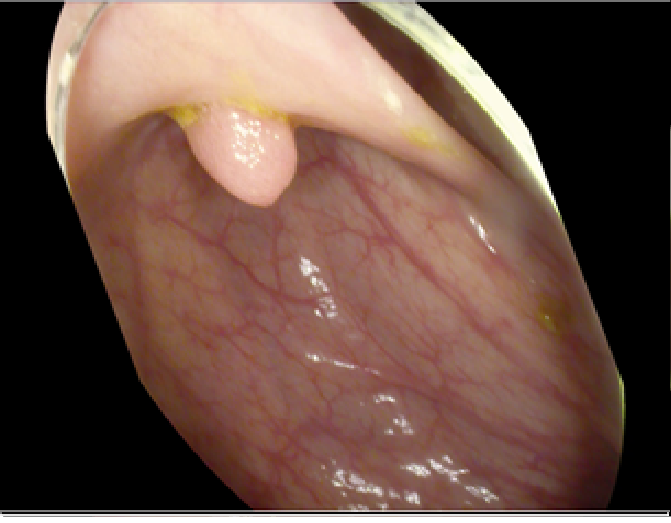

The study used a publicly available dataset of polyp-frames obtained from the ETIS-Larib database [34], containing 196 polyp images. These images were obtained from 34 different colonoscopy videos of 44 different polyps with various appearances and sizes, having a resolution of pixels. The ground truth of polyp areas for polyp datasets is determined by expert video endoscopists. A CNN model trained with such a small amount of data is likely to be meaningless and unstable, so data augmentation was performed on the polyp dataset. Data augmentation had to be performed on the colonoscopy images by considering vivid variations. Otherwise over-fitting would have occurred. In a colonoscopy imagery, polyps exhibits large variations in location, color, and scale. Moreover, variations in brightness and definition also occur due varrying the view-point of the camera. Therefore, in addition to photometric distortions and geometric distortions, we also have considered zooming, shearing, and altering brightness as strategies for data augmentation.

For photometric distortions, we controlled brightness and contrast as an enhancement, while blurring by adding noise with a standard deviation of 1.0. Similarly, for geometric distortions, clock-wise rotation of the polyp images with angles of , , and were performed. Zoom-in and zoom-out with zooming parameters such as 30.00% and 10.00% were performed to obtain different scales of polyp images. Lastly, shearing for both the x-axis and the y-axis was performed to shear the images from left to right and top to bottom, respectively. Fig. 4 shows photometric and geometric forms of image augmentation. In this way, we augmented the data set of the ETIS-Larib database from 196 polyp images to 2,156 images, which is more suitable for training the proposed deep CNN model.

The results shown in Fig. 6 are generated using the proposed deep CNN model on the augmented data set. It can be observed that the proposed model shows better polyp detection performance. As illustrated in Fig. 6, polyps within a frame can be identified at multiple positions, and as noted above in this case, the TP for detection is considered to be 1. The proposed deep CNN model performed better than other benchmark results in terms of the performance metrics listed above, as shown in Table. 2 and Fig. 6.